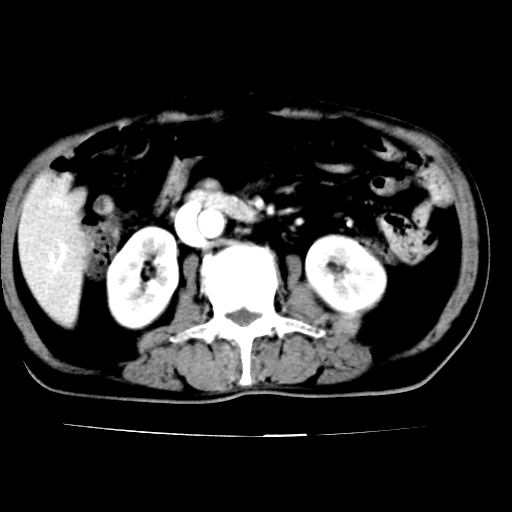

男,75岁,腹痛月余,彩超发现脐周腹主动脉异常回声。临床诊断:腹主动脉瘤。

ct诊断:右骼总动脉囊性动脉瘤并瘤内附壁血栓形成,与下腔静脉之间形成动静脉瘘。

请问各位老师:能排除动脉瘤破裂的可能吗?

各位老师注意到下腔静脉的充盈缺损了吗?注意到动静脉漏了吗?

当时是扫描的标准动脉期,可是下腔静脉与腹主动脉同步强化且幅度一致。所以我想动静脉瘘是存在的。